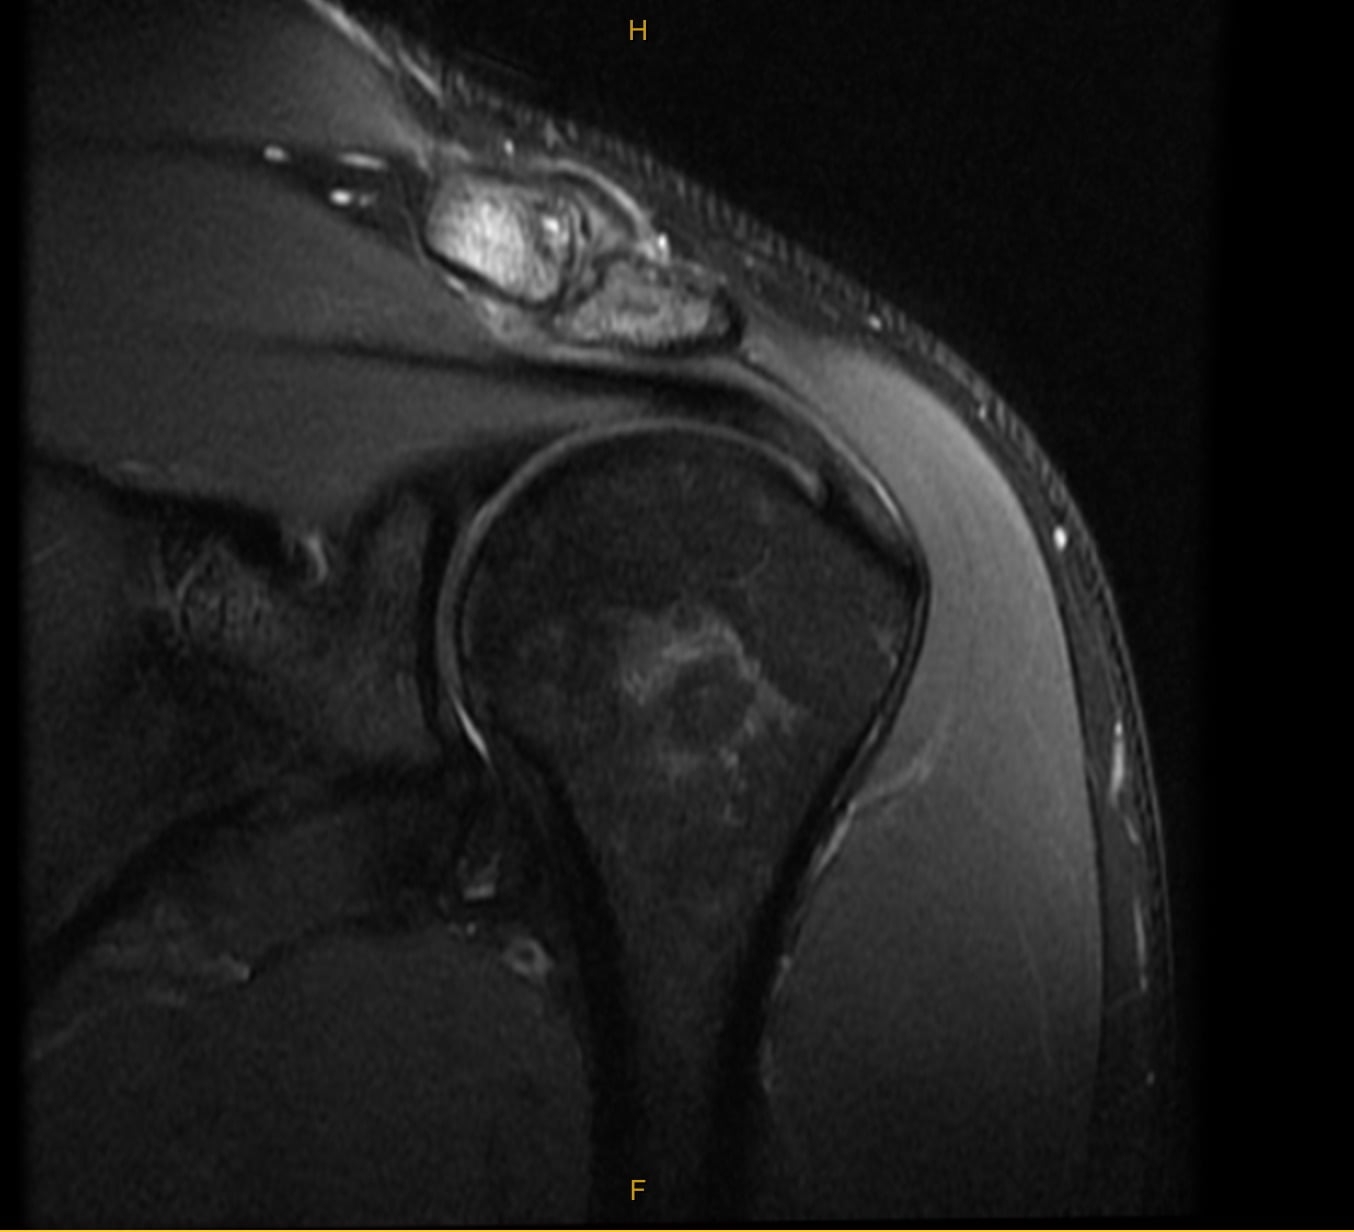

Preoperative MRI of patient clavicle to receive Distal Clavicle Resection (Mumford Procedure)